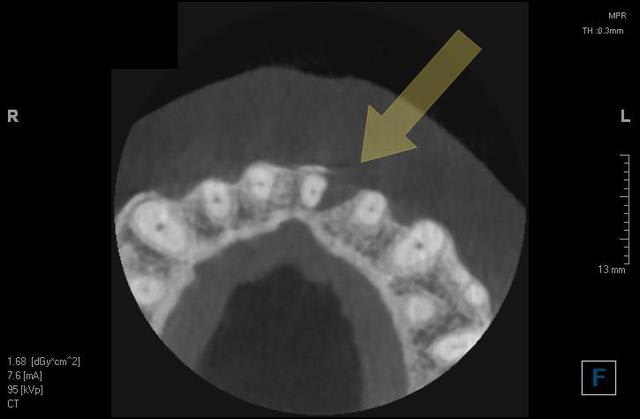

Sagital jxcd3g - Eugenol

Coupe wivo5x - Eugenol

3d gxwzhi - Eugenol

Image r6habu - Eugenol

Thomas Crown

16/10/2014 à 12h41

Humator, une image avec métal si tu peux, pour voir les artefacts et qualité de résolution.

Merci!

Humator t9r5wy - Eugenol

humator

16/10/2014 à 15h19

voilà un cas avec du metal:couronnes sur les dents bordant l'édentement, et en haut. c'est sur la reconstruction 3d que ça perturbe le plus. Cela dit, tu peux "couper" les artefacts pour les faire disparaitre, si tu souhaites une belle image en volume.

C'est vrai que certaines reconstitutions 3d sont plus moches, quand il y a beaucoup de métal, mais ça ne perturbe pas les coupes.

j'essaye de t'en trouver d'autre bien moches...

ici je n'ai pas "nettoyé" la reconstruction 3d

--

N.Hum